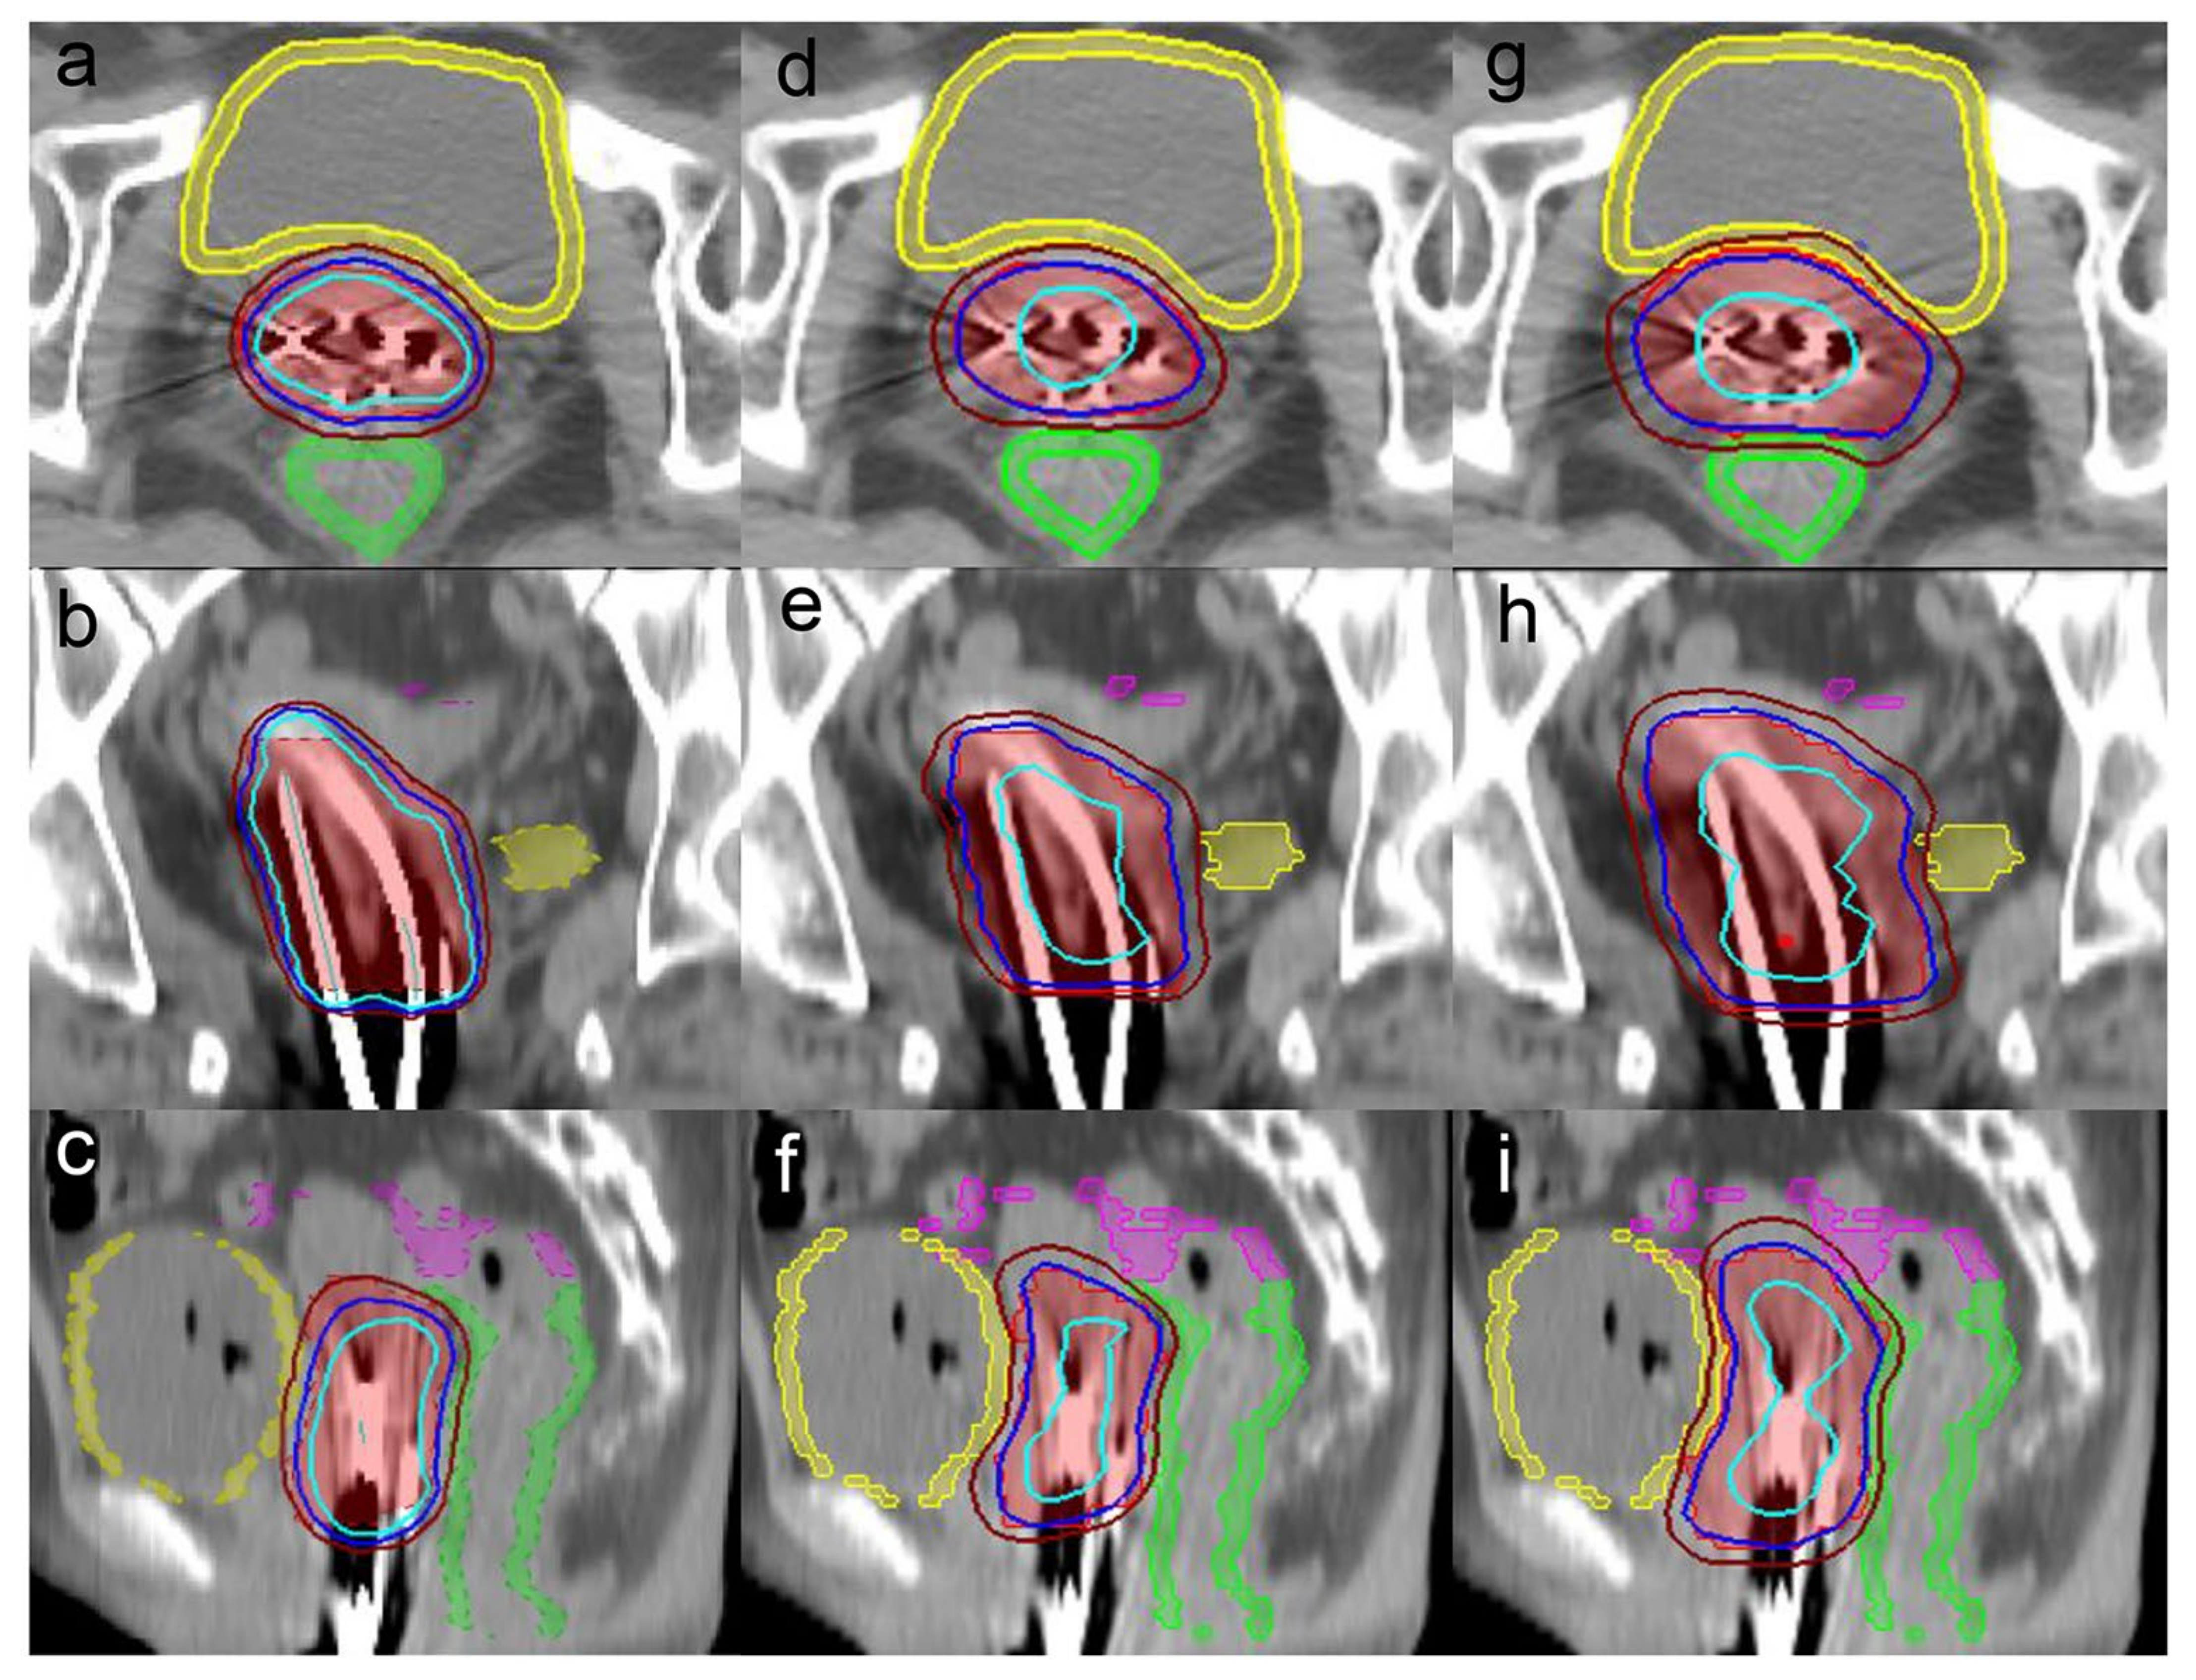

2.4. CyberKnife Planning

2.5. Evaluation of the Treatment Plans